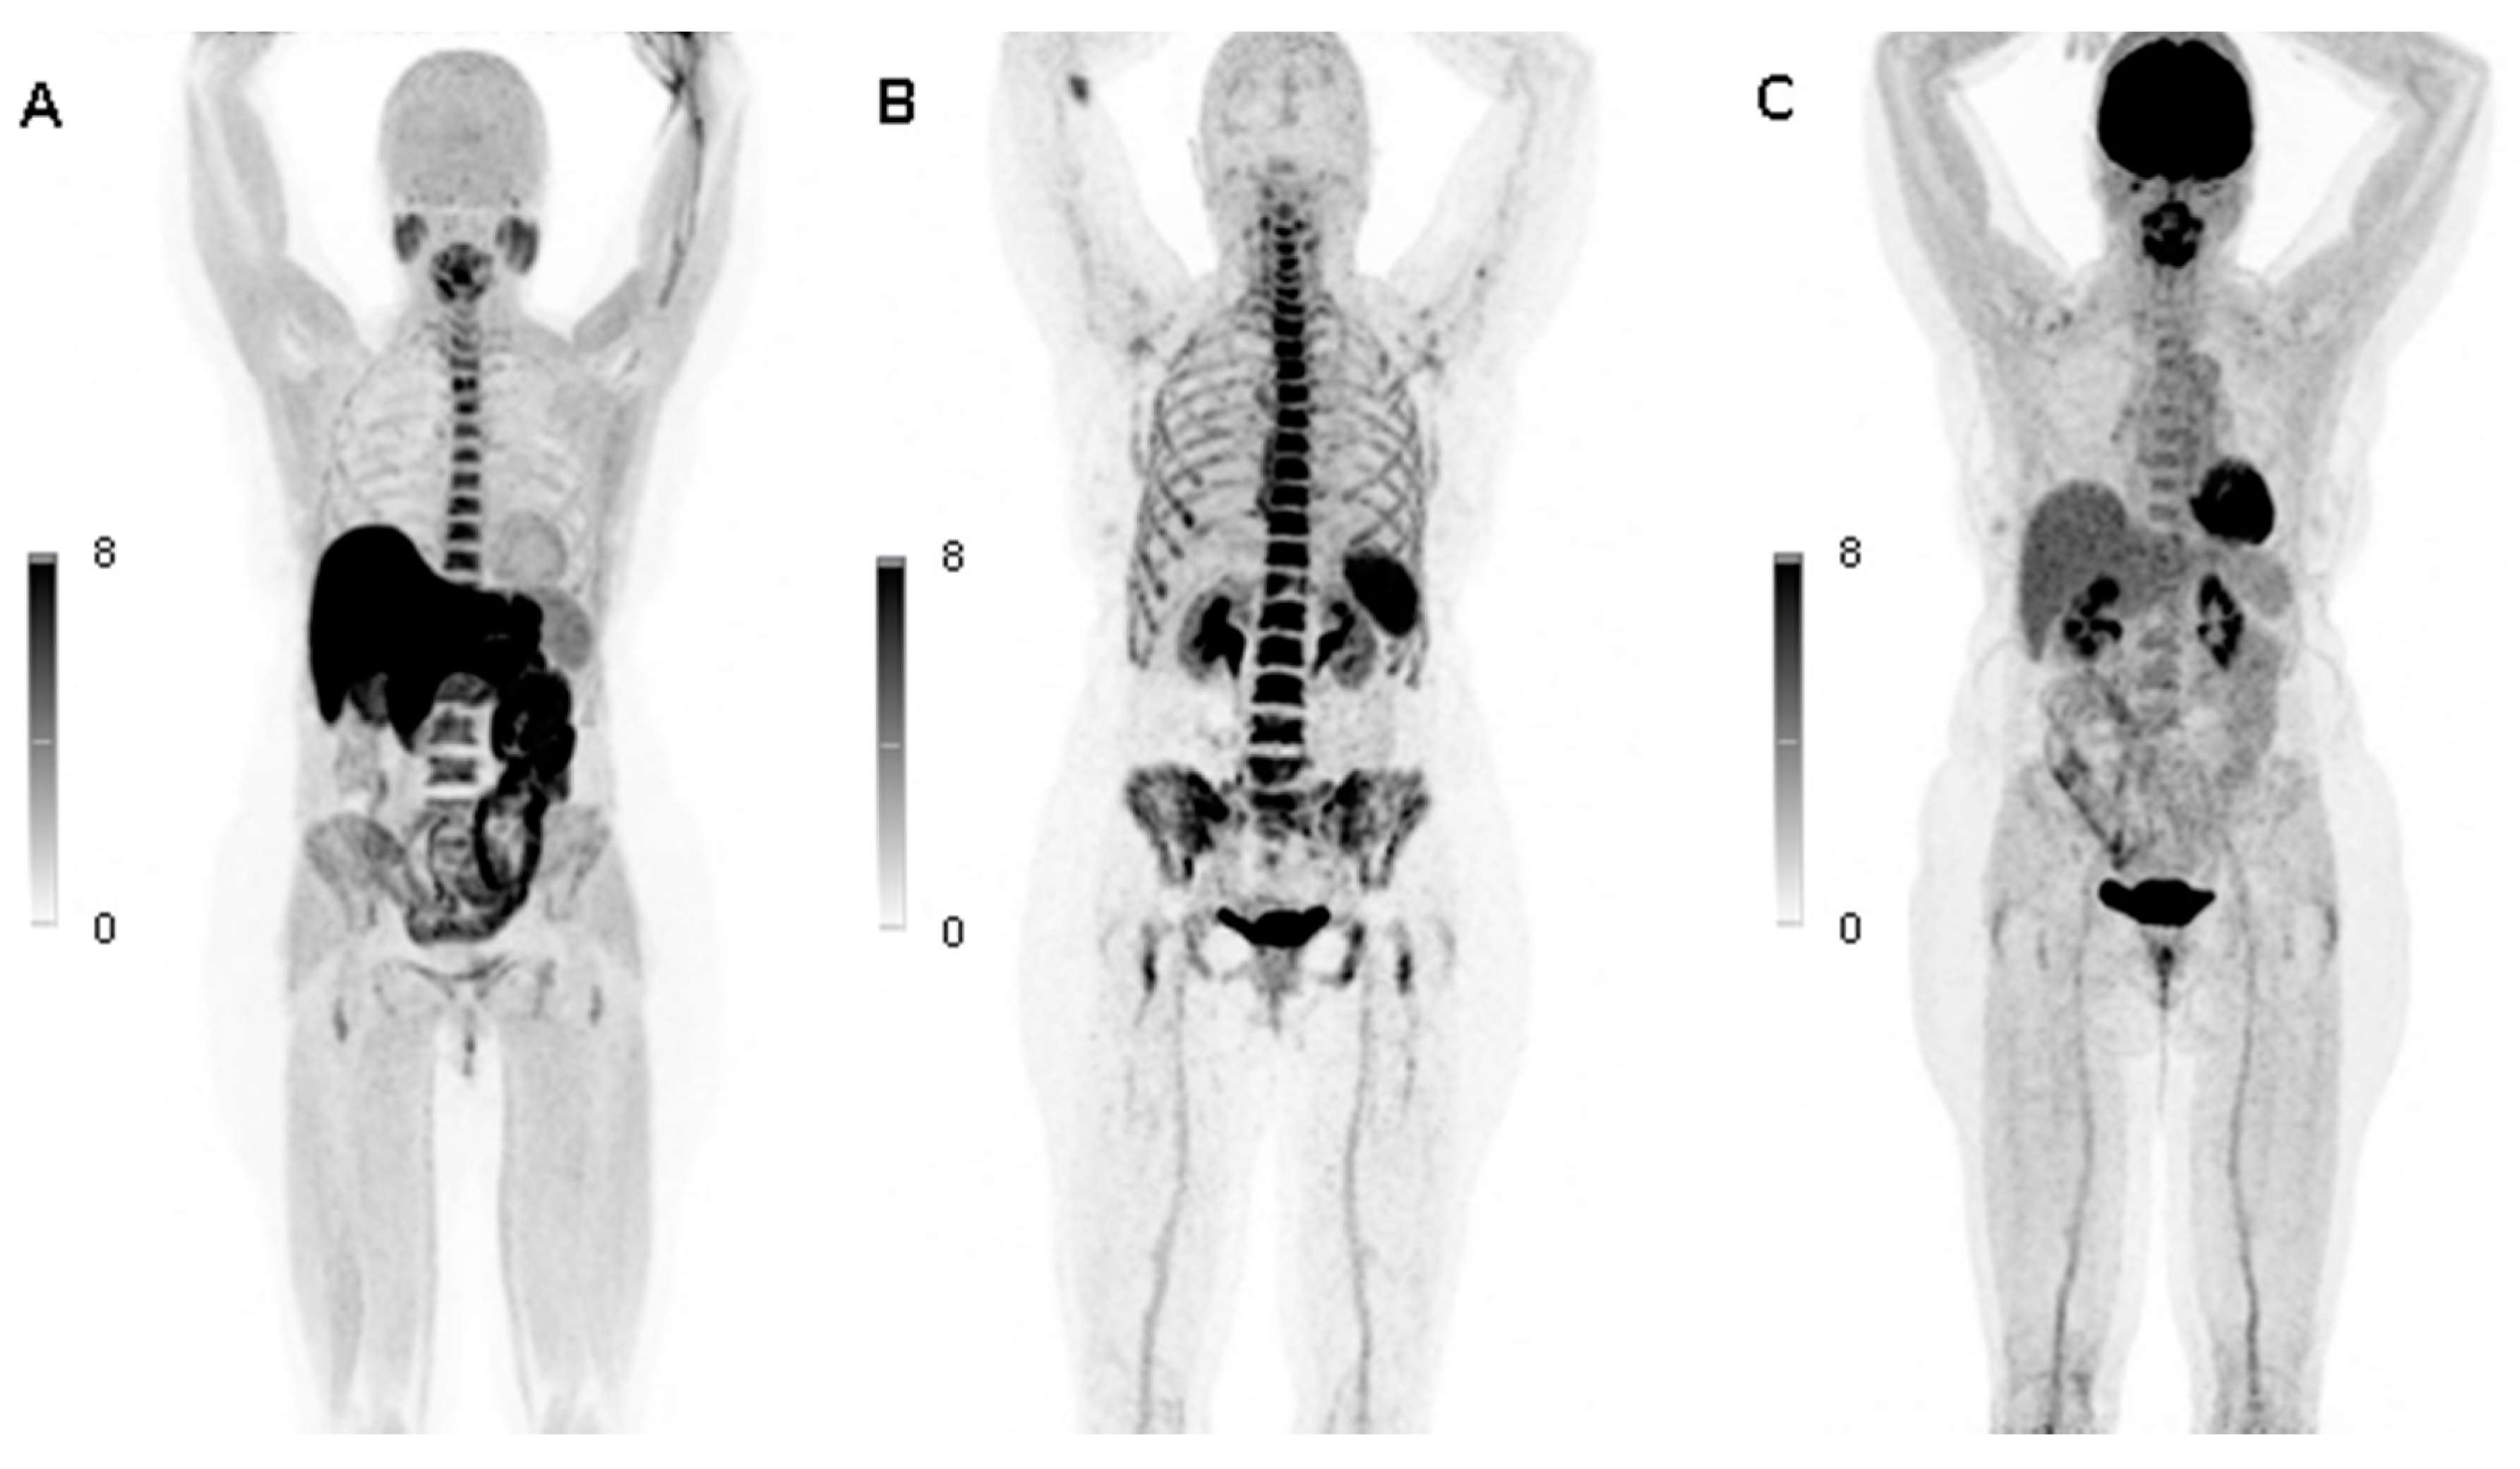

| Case | 18F-FDG PET/CT | 11C-Methionine PET/CT | 68Ga-Pentixafor PET/CT | |||||||||||||||

|---|---|---|---|---|---|---|---|---|---|---|---|---|---|---|---|---|---|---|

| PET | SUVmax of LV L2-L4 | SUVmean of LV L2-L4 | SUVmean in RA | TBRmax | TBRmean | PET | SUVmax of LV L2-L4 | SUVmean of LV L2-L4 | SUVmean in RA | TBRmax | TBRmean | PET | SUVmax of LV L2-L4 | SUVmean of LV L2-L4 | SUVmean in RA | TBRmax | TBRmean | |

| 1 | neg | 4.50 | 3.44 | 2.33 | 1.93 | 1.47 | pos | 6.85 | 5.59 | 0.86 | 7.97 | 6.50 | pos | 12.82 | 7.99 | 1.98 | 6.47 | 4.03 |

| 2 | neg | 2.83 | 1.98 | 2.28 | 1.24 | 0.87 | neg | 3.33 | 2.54 | 1.46 | 2.28 | 1.74 | neg | 4.46 | 2.67 | 1.91 | 2.33 | 1.40 |

| 3 | neg | 2.26 | 1.39 | 1.04 | 2.18 | 1.34 | neg | 3.36 | 2.21 | 1.30 | 2.58 | 1.70 | neg | 4.31 | 1.60 | 1.82 | 2.37 | 0.88 |

| 4 | neg | 3.68 | 2.33 | 2.66 | 1.38 | 0.87 | neg | 4.38 | 2.96 | 1.22 | 3.59 | 2.42 | pos | 11.71 | 3.23 | 1.70 | 6.89 | 1.90 |

| 5 | neg | 1.66 | 1.08 | 1.56 | 1.07 | 0.69 | pos | 2.62 | 1.76 | 0.66 | 3.97 | 2.67 | neg | 3.28 | 1.63 | 1.16 | 2.83 | 1.40 |

| 6 | neg | 2.35 | 1.68 | 1.41 | 1.67 | 1.19 | neg | 4.09 | 2.44 | 0.47 | 8.71 | 5.19 | pos | 6.99 | 4.40 | 2.17 | 3.22 | 2.03 |

| 7 | neg | 3.34 | 2.04 | 1.49 | 2.24 | 1.37 | neg | 5.07 | 3.16 | 1.20 | 4.22 | 2.63 | neg | 5.25 | 2.64 | 1.17 | 4.48 | 2.26 |

| 8 | neg | 3.16 | 2.18 | 1.61 | 1.96 | 1.35 | neg | 5.02 | 3.46 | 1.06 | 4.74 | 3.27 | neg | 5.90 | 3.17 | 1.86 | 3.17 | 1.71 |

| 9 | neg | 3.29 | 2.23 | 1.54 | 2.14 | 1.45 | neg | 5.76 | 4.07 | 0.87 | 6.62 | 4.67 | pos | 7.09 | 4.32 | 1.49 | 4.76 | 2.90 |

| 10 | neg | 2.45 | 1.59 | 1.85 | 1.32 | 0.86 | neg | 3.35 | 2.47 | 1.26 | 2.66 | 1.96 | pos | 4.73 | 2.96 | 2.34 | 2.02 | 1.27 |